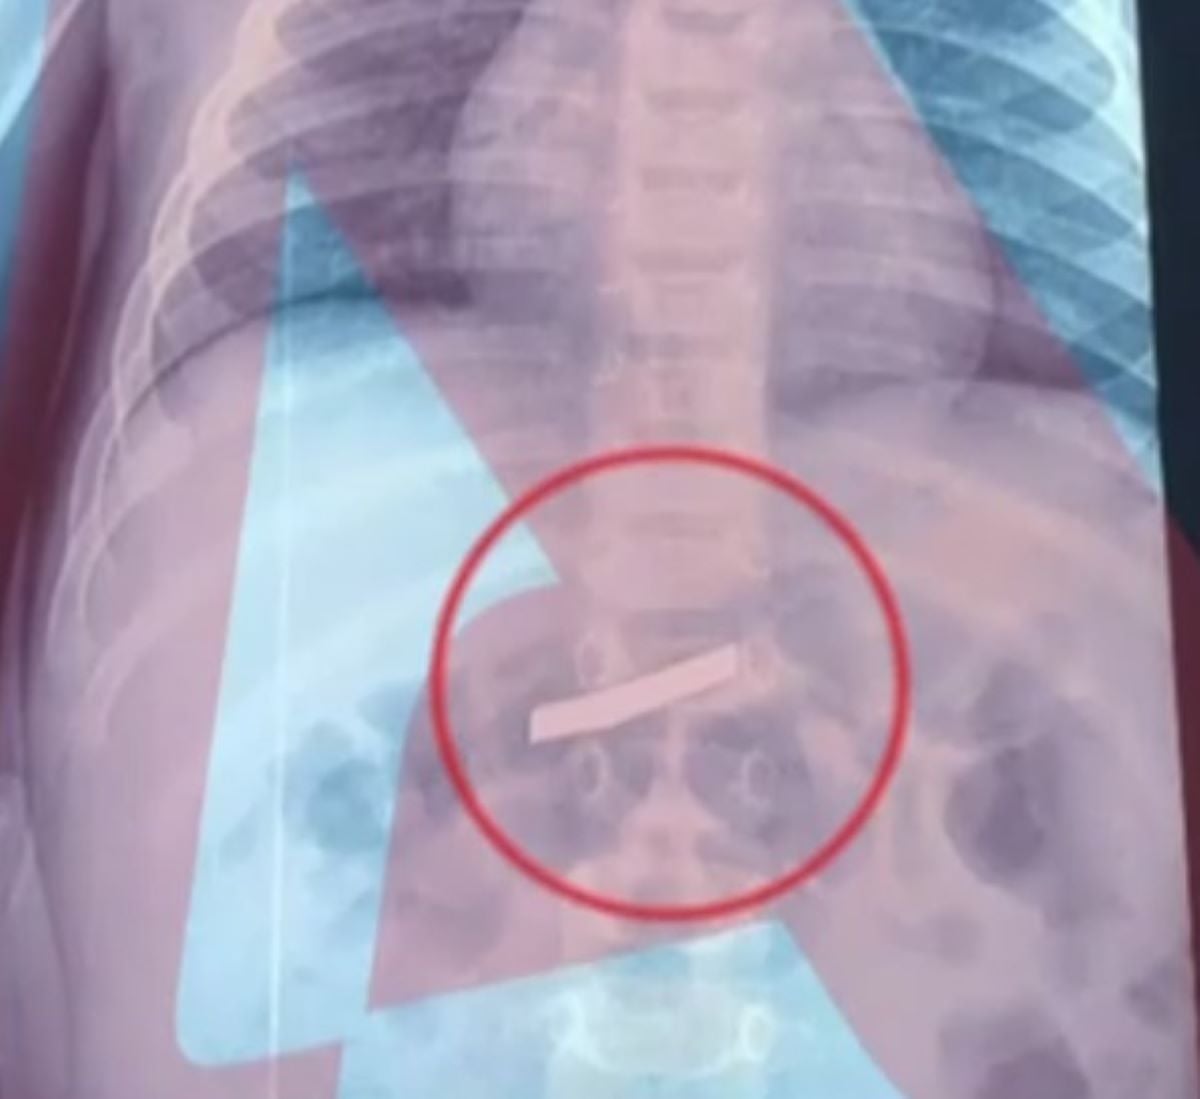

Στις δέκα το πρωί της Τετάρτης το παιδάκι χρειάστηκε να μεταφερθεί στο Παίδων κι εκεί, από την ακτινογραφία που έγινε, διαπιστώθηκε ότι όντως το τρίχρονο είχε καταπιεί ένα ξυράφι. Η ακτινογραφία έγινε για να εντοπίσουν το ακριβές σημείο μέσα στο σώμα όπου βρισκόταν το πολύ επικίνδυνο αντικείμενο.

Η ακτινογραφία έδειξε πως είχε φτάσει στην κοιλιά του.